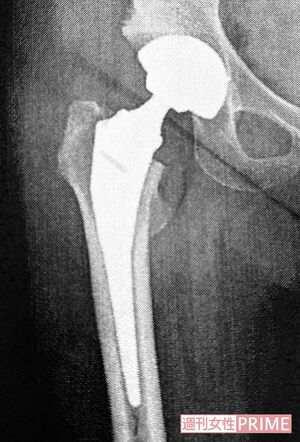

3年前、変形性股関節症で両脚の人工股関節置換術を受けた歌手の岡崎友紀さん。実は40代から股関節に痛みを感じていたが無理をして動いていたのだそう。「痛みもなくなり、スタスタ歩けるようになったことがもう、うれしくて」と話す岡崎さんが一大決心して臨んだ手術、そしてリハビリ生活について語った。